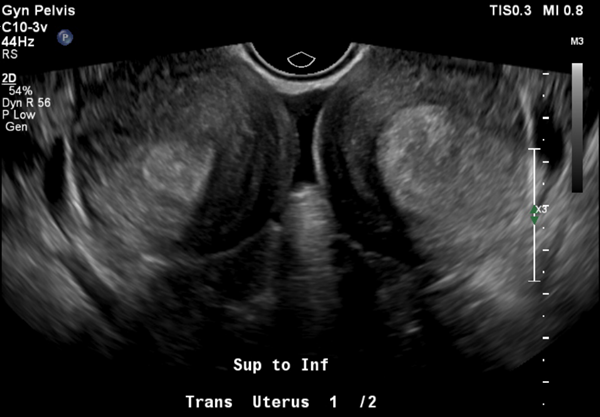

Does this patient have a normally developing pregnancy by ultrasound?

Answer:

No, the snowstorm appearance in both uterine cavities is not consistent with her quantitative hcg; there is also no evidence of a gestational sac or normal intrauterine pregnancy.

Further pathology of this patient’s uterine contents revealed immature chorionic villi in the left uterine horn with endometrial tissue in the right uterine horn. The report also specified that a very early complete hydatidiform mole and invasive mole must be ruled out, therefore lacking a definitive diagnosis. Clinically, the presentation was consistent with a molar pregnancy.

This patient had two uncommon pathologies: presumed gestational trophoblastic disease and uterine didelphys. Gestational trophoblastic disease encompasses a spectrum of premalignant to malignant gestational tissue. Rates are difficult to obtain, as there seems to be wide temporal variation, but estimates for hydatidiform mole in particular are estimated to be between 0.57 and 2 per 1000 pregnancies. Ultrasound and laboratory findings such as quantitative beta HCG are mainstays of early identification and treatment. Ultrasound is not very sensitive as a diagnostic modality, but it does have high positive predictive value.1 In this patient, the mismatch in quantitative beta HCG value, last menstrual period date, ultrasound findings, as well as the patient’s postpartum period combined with depo-provera birth control led our team to be exceedingly concerned for gestational trophoblastic disease (GTD). Unchecked, GTD can lead to increased uterine size and bleeding, to endocrine abnormalities, and even to invasive central nervous system lesions and death; however, with treatment and early diagnosis complete resolution nears 100% in women.2 It is important to remember to include a chest x-ray in your workup for screening in a patient with suspected gestational trophoblastic disease to determine staging and appropriate treatment. For example, if lung lesions are visible, the patient would require CT Chest/Abdomen/Pelvis and brain MRI to determine staging.3 If found to have metastatic disease, these patients likely need chemotherapy.4 This changes the level of subspecialty care the patient needs.